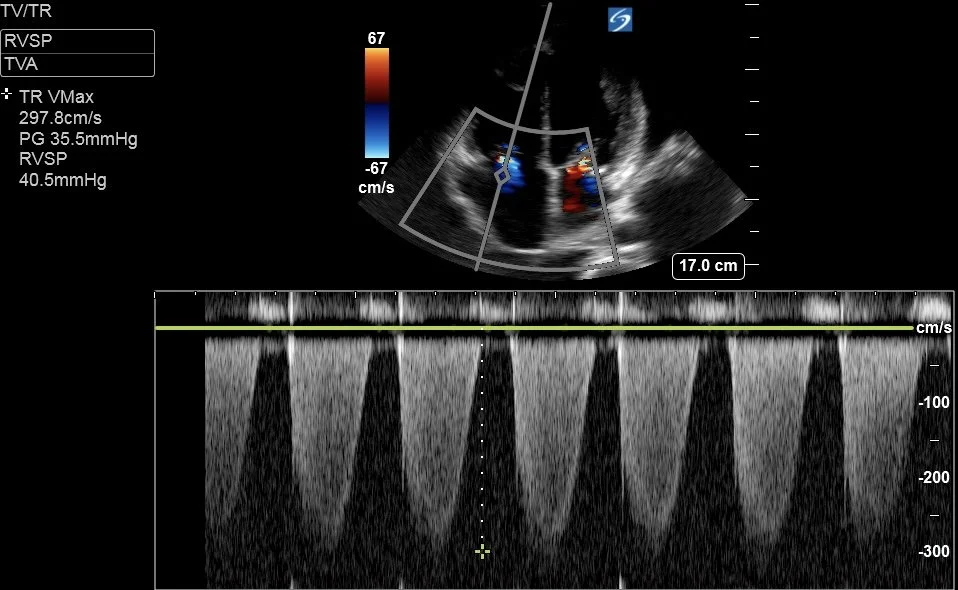

Below is the CW doppler trace of the Tricuspid Regurgitation jet, and a clip of the IVC view.

Can you estimate the pulmonary artery systolic pressure (PASP)?

Remember that PASP = RVSP + RAP

RVSP [RV systolic pressure] is measured from the TR Vmax - this is 40.5mmHg as calculated by the machine.

RAP is estimated from IVC size and collapsibility with respiration. As a rule of thumb:

• If IVC <2.1cm and:

• collapses >50% —> RAP = 5mmHg

• collapses <50% —> RAP = 8mmHg

• If IVC >2.1cm and:

• collapses >50% —> RAP = 8mmHg

• collapses <50% or plethoric —> RAP = 12mmHg

Here RAP was estimated at 12mmHg

Thus PASP = 40.5 + 12 = 52.5mmHg

This is classed as moderate PHN, but in the setting of a “low-flow state” this represents Severe Pulmonary Hypertension.